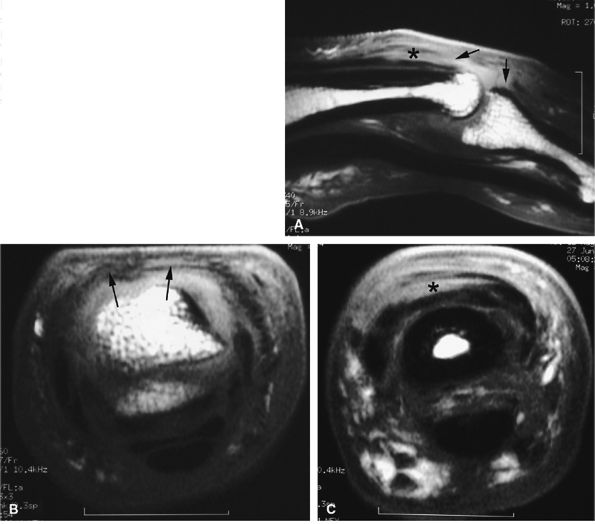

![]() |

|

FIGURE 11.22 ● Associated injuries of the volar plate and a collateral ligament of the PIP joint. (A) Sagittal T1-weighted and (B) axial post-contrast fat-suppressed T1-weighted images show proximal injury of the checkreins of the volar plate with associated synovitis (white arrows). Continuity of the central slip of the extensor tendon is seen (arrowheads), and there is a tear of the radial collateral ligament (asterisk).